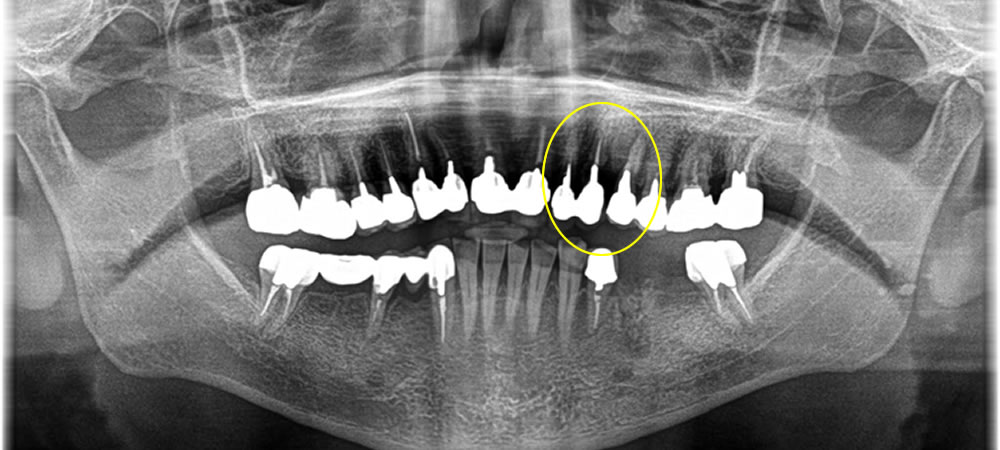

歯根に膿が溜まった歯を抜歯してインプラントで治療した症例

年齢

30代

性別

女性

症例を見る